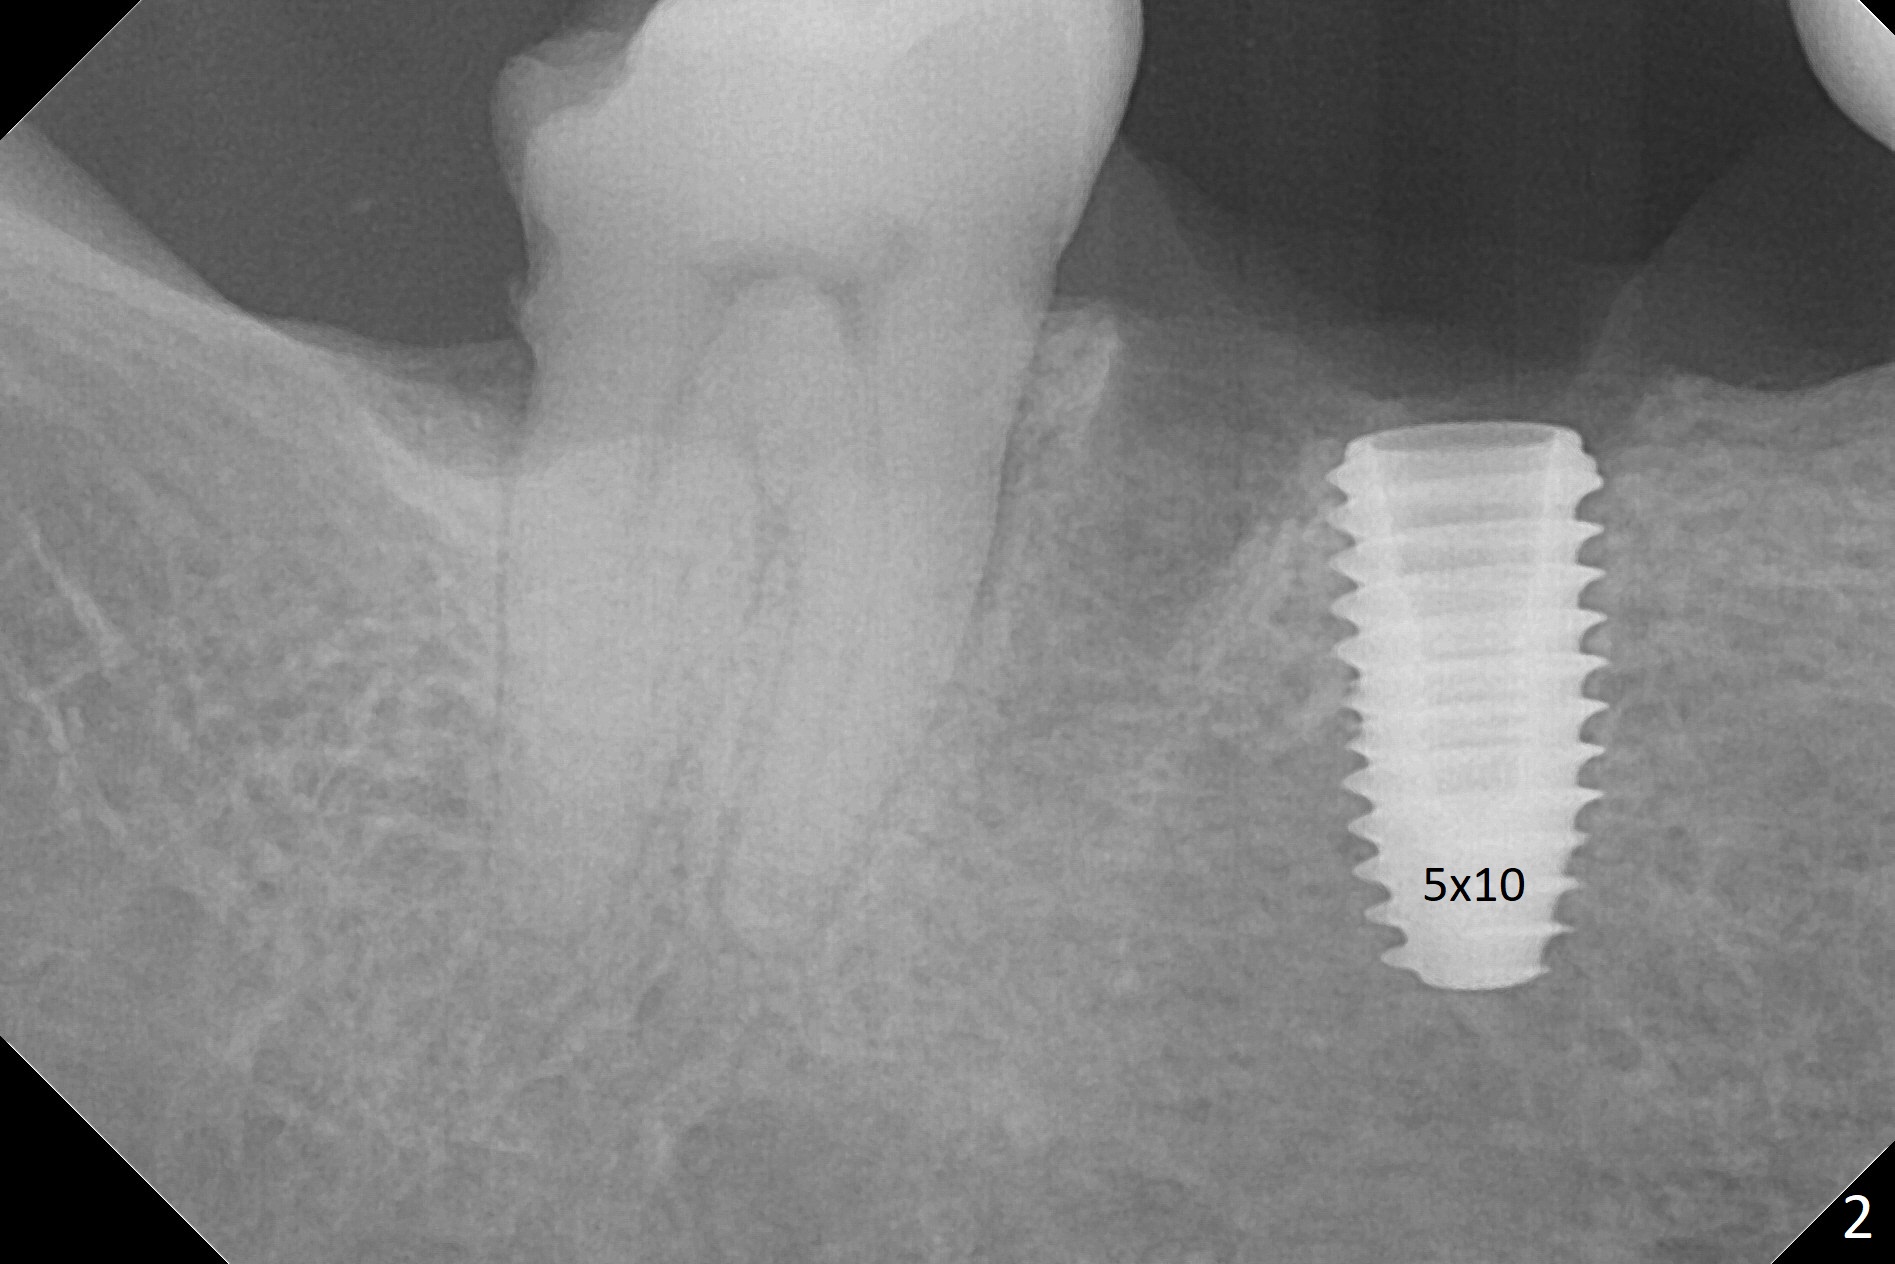

Because of severe pain, block anesthesia is administered prior to extraction. The mesial socket of the tooth #30 is deep with granulation tissue. A 4.5x10 mm dummy implant is placed with < 40 Ncm following sequential osteotomy until 4x13 mm over the septum (Fig.1 (low density)). After 4.5x13 mm drill, a 5x10 mm dummy implant is inserted with <40 Ncm (Fig.2). Since the Inferior Alveolar Canal is invisible (Fig.1,2 (pan should have been taken)), a 5x11.5 mm implant is placed with <20 Ncm. When a 6.5x5.5(3) mm abutment is placed, the underlying implant is turned (Fig.3). With collagen plug is placed in the distal socket and Vera graft around the implant, an immediate provisional is fabricated and relined. When it is seated, it has mobility. In fact the provisional should be locked into the edentulous area while it is malleable. To prevent low primary stability, osteotomy should be under prep, since the implant (red circle) contacts only two bony surfaces, i.e., the mesial (M) and distal (D) walls of the mesial socket (Fig.4 (occlusal view) black oval). There are gaps buccally (B) and lingually (L). In case of low stability, a healing screw or abutment should be placed; the remaining socket is closed with suture. The provisional is loose 19 days postop; it is removed by sectioning. A healing screw is placed. Twelve days later, the wound heals (Fig.5). The patient returns for uncover 8 months postop; although the implant has osteointegrated apparently, the crestal bone resorbs to the implant plateau level (Fig.6 arrow). It seems that the immediate implant should be routinely placed 2-3 mm deeper. The open margin is closed with composite when the abutment/crown is removed after cementation (Fig.7).